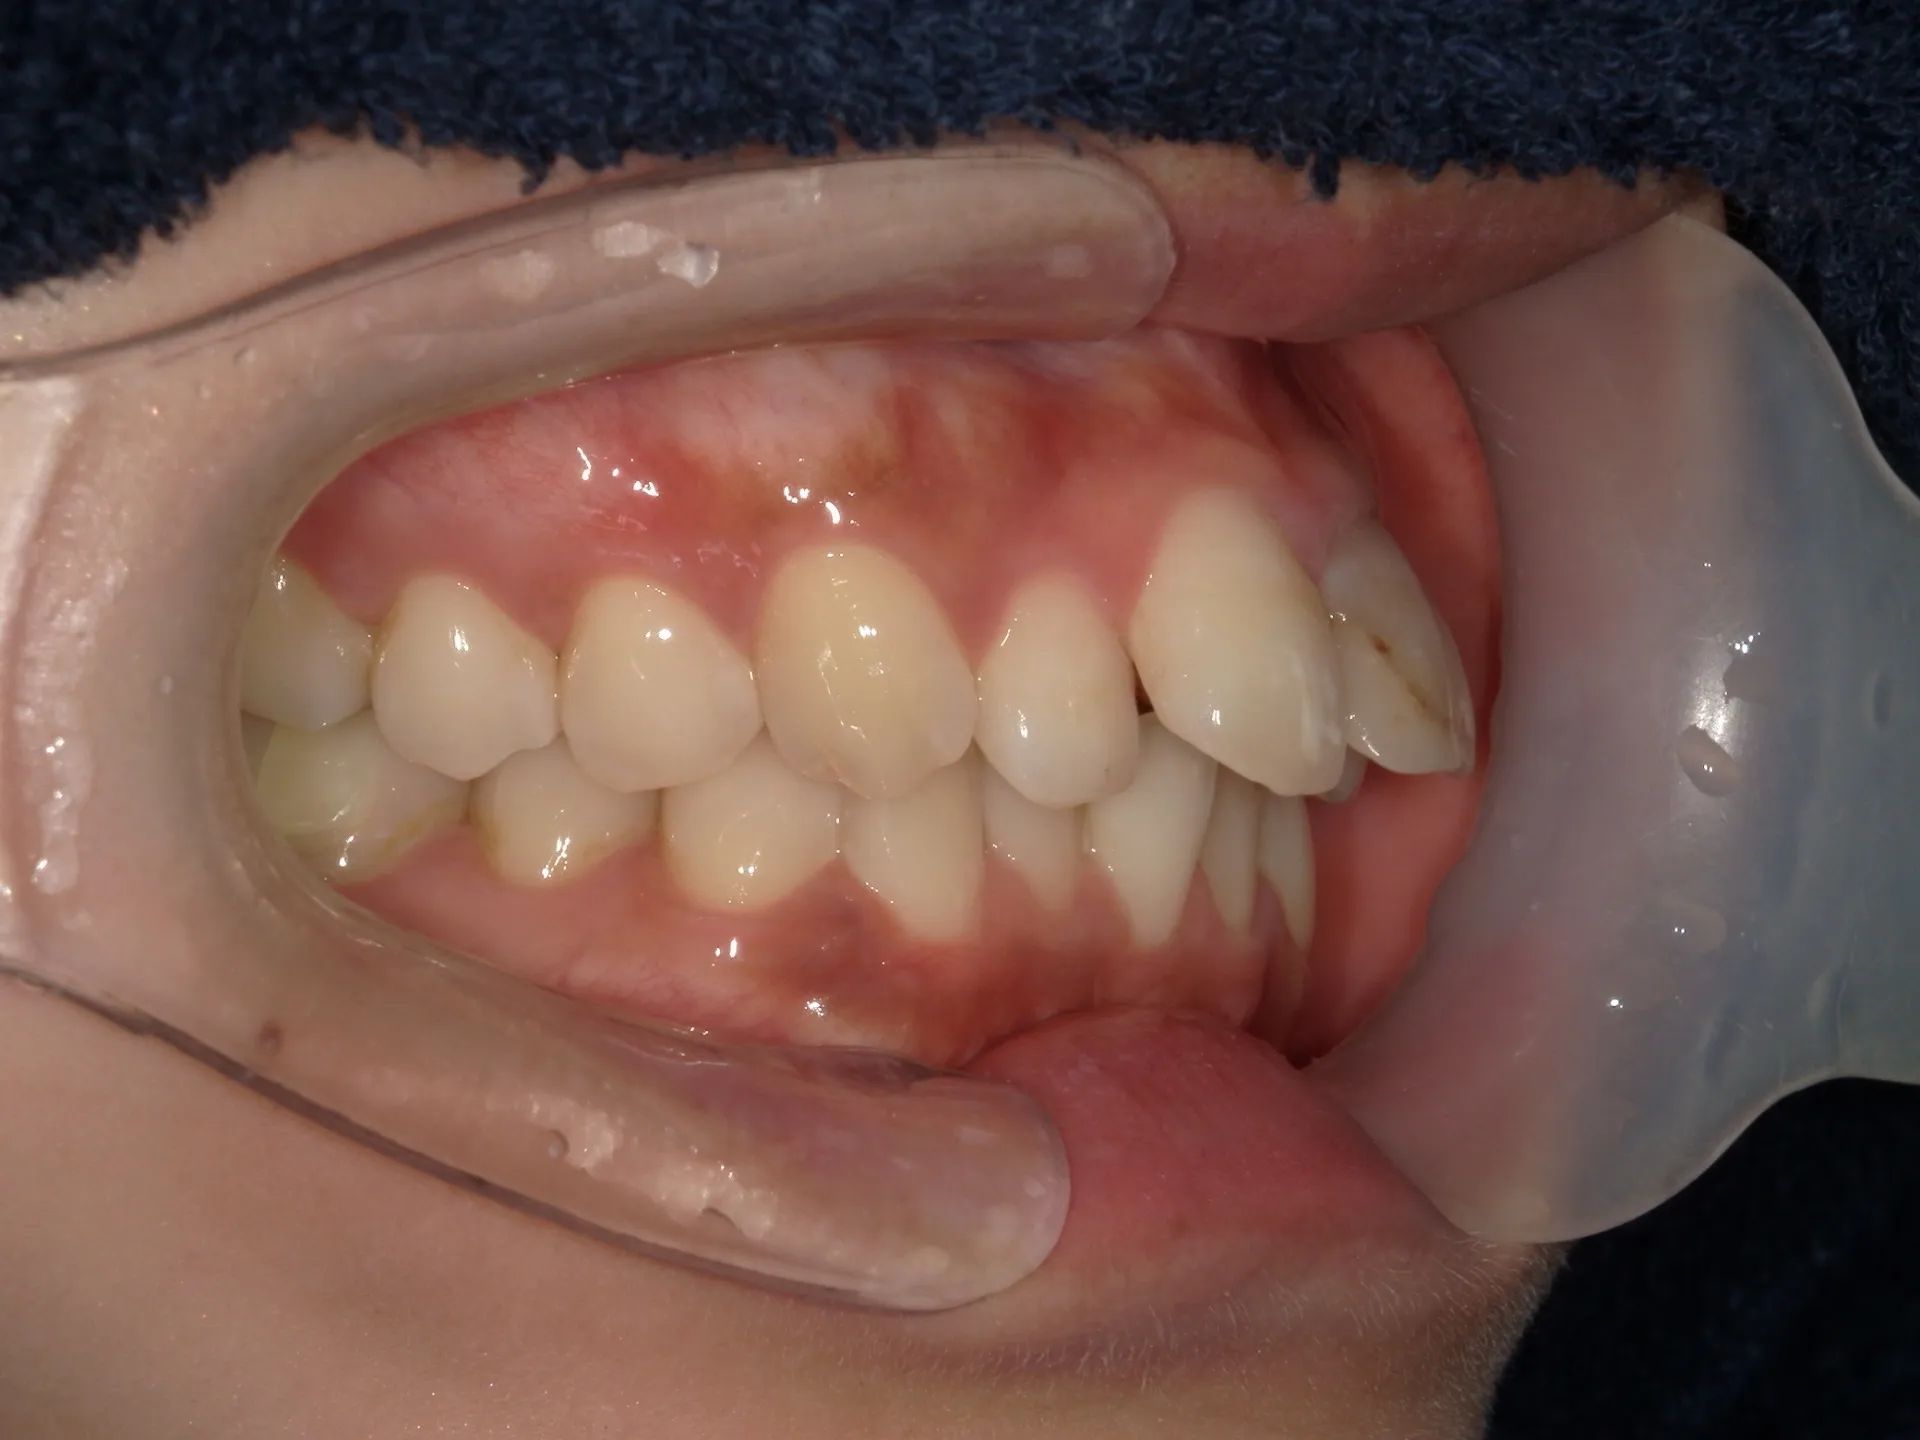

大きく飛び出してしまった前歯の矯正と変色の治療を希望された症例をご紹介いたします。

しかしながら、患者様が遠方に引越すことになり当院での治療はここで終了となってしまいました。

もう少しで矯正も歯の変色も変えられることができたのですが、移動費もままならないので残念ながら転医として他の歯医者さんで引き継いでいただく形となりました。